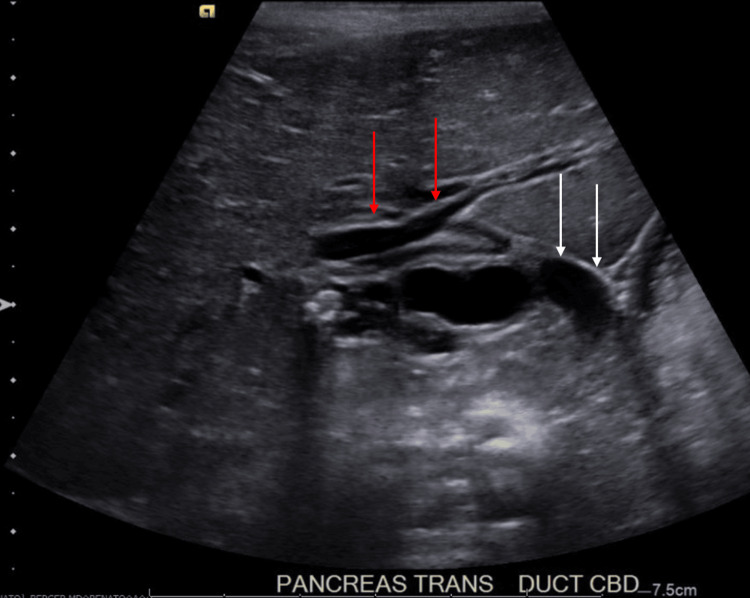

In the ED, the patient was afebrile and hemodynamically stable. Her physical examination findings included mild hepatomegaly, mild abdominal tenderness without peritoneal signs, and the presence of a well-healed surgical scar on the abdomen with an underlying abdominal hernia. Laboratory studies were significant for leukocytosis, transaminitis, direct hyperbilirubinemia, and hyperlipasemia. Specific values are displayed in Table 1. Abdominal US showed several gallstones and mild to moderate intra- and extrahepatic biliary ductal dilatation likely due to a stone in the distal common bile duct (CBD) (Figure 1).

After admission, the patient was started on ursodiol, piperacillin-tazobactam, and maintenance intravenous fluids containing dextrose. A nothing by mouth (NPO) order was also placed in preparation for imaging under sedation. The following morning, MRCP was completed, showing the common hepatic duct measuring 13 mm and a 9×5 mm stone in the distal common bile duct (Figure 2).